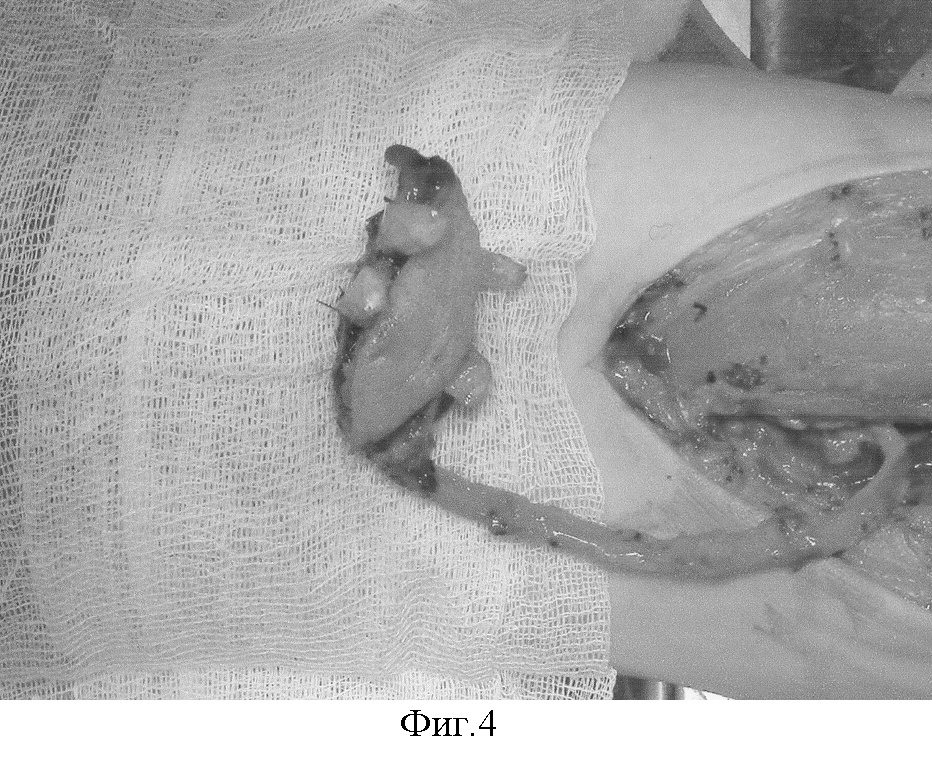

Фиг.6 – единый комплекс тканей фиксирован в реципиентной области. Фрагменты хряща фиксированы к хрящам трахеи.